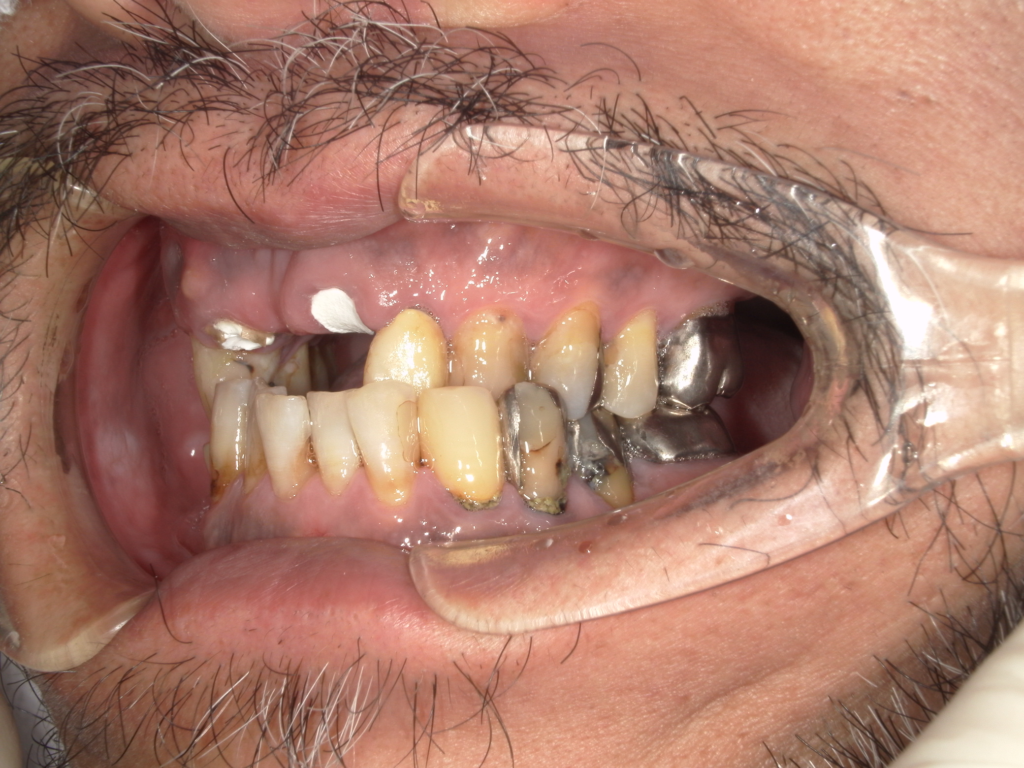

Y様インプラント実例 #44

左の上下の奥歯をインプラントで治療しています。

左下の奥歯は歯を抜くのと同時にインプラントの埋め込みを行っています。

被せものは上下、セラミックスで作っています。

治療前

治療後